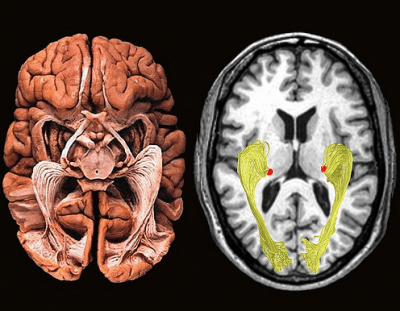

Uitgelicht 3d Mri Of Human Brain A External Coronal View 3d Model B External Download Scientific Diagram